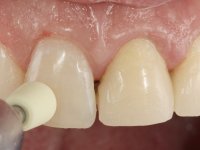

Foi feito o tratamento endodôntico dos dentes 2.1 e 2.2.de imediato, a sintomatologia que o paciente manifestava a isso impunha. Na mesma consulta foi realizada uma extensa gengivetomia com o bisturi elétrico, no sentido de expor os limites cervicais da fratura. Foram colocadas resinas compostas nos remanescentes radiculares com a intenção de reformular a emergência dos tecidos moles. Realizei a impressão dos remanescentes radiculares para confeção em laboratório de uma ponte provisória. A ponte provisória de 2 elementos, apresentava um formato que visava no futuro acomodar o coto dos espigões falsos cotos que iria ser cimentados nos remanescentes radiculares. Apresentava um reforço metálico palatino e dois apoios para os dentes adjacentes, um mesial e outro distal. Os remanescentes radiculares foram preparados para a confeção de dois espigões falso coto fundidos. As linhas de acabamento cervical foram definidas e os canais radiculares desobturados e preparados. A impressão foi realizada com a utilização de tutores de plástico com a técnica de dupla mistura. O afastamento gengival foi feito utilizando pasta de caolino. A ponte provisória foi rebasada em boca com acrílico auto polimerizavel, cimentada provisoriamente sobre as raízes e os apoios colados aos dentes adjacentes. No laboratório foram confecionados os E.F.C. fundidos, tendo o cuidado de preservar espaço para a definição no re preparo dentário da linha de acabamento cervical. Removida a ponte provisória foi feita a cimentação dos E.F.C. fundidos com cimento de ionómero de vidro reforçado com resina. A ponte provisória teve que ser retocada para permitir a acomodação dos cotos e simultaneamente foi readaptada à redefinida linha de acabamento cervical. Durante 2 meses a ponte provisória acompanhou a estabilização periodontal das raízes traumatizadas e simultaneamente conseguiu a maturação da arquitetura gengival.

Durante esse período foi também removida a férula dos dentes 1.3, 1.2 e 1.1 no sentido de avaliar a sua estabilidade. Esta remoção foi feita com muito cuidado para não danificar a superfície vestibular dos dentes. Foram utilizados discos de polimento de forma sequencial e taças de borracha. Após a repetição de testes de vitalidade verificou-se a necrose do dente 1.1, tendo sido realizado o necessário tratamento endodôntico. A impressão definitiva foi feita com a técnica de dupla mistura e o caolino utilizado como afastamento gengival. A ponte provisória foi mais uma vez rebasada. No laboratório, utilizando a tecnologia CAD-CAM, foi feita uma infraestrutura em Zr e posteriormente revestida com cerâmica. Durante este processo sentimos a necessidade de acrescentar resina composta por mesial do dente 2.3 com o objetivo de manter os diâmetros mesio-distais simétricos aos dentes do 1.1 e 1.2. Nesse sentido foi confecionada uma chave de silicone transparente que seria utilizada em boca para orientar esse acrescento. Na porção mesial da superfície palatina do dente 2.1 da ponte foi feita uma pequena cavidade que seria utilizada para colocar uma pequena férula de arame com o objetivo de assegurar a eventual abertura de um diastema. Em boca foi realizado um isolamento relativo e feito o acrescento de resina composta no 2.3 com a ajuda da chave de silicone. A ponte foi cimentada definitivamente com cimento de ionómero de vidro reforçado com resina. Finalmente foi colado uma pequena porção de arame entre a ponte e o dente 1.1.